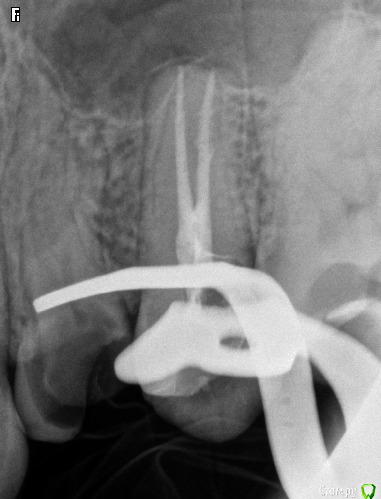

SSTi Опубликовано 16 декабря, 2014 Автор Поделиться Опубликовано 16 декабря, 2014 44 зуб страшилка. Все стандартно. Упор 45. 6 Ссылка на комментарий